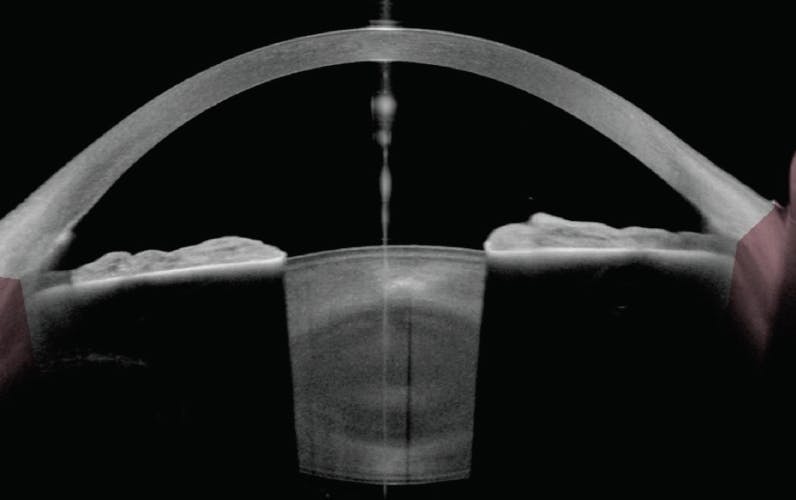

In this case, however, the relative stability of the right eye after LPI compared to the left eye prompted me to perform an LPI in the left eye. Postoperatively, the posterior bowing of the iris resolved (Figure 7), but the IOP remained at 20 mm Hg. The patient is scheduled to undergo SLT followed by repeat home tonometry to determine if IOP fluctuations decrease.